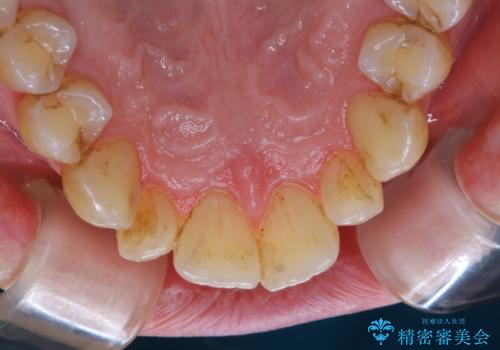

- かなり久しぶりの来院とのことで、クリーニング希望でした。全体的に汚れの付着があったため、PMTCの60分コースを行いました。

PMTCとは、プロフェッショナル・メカニカル・トゥース・クリーニングという、専門家による機械的な歯のクリーニングです。 PMTCは、歯磨きだけでは落とすことのできない細菌・バイオフィルムを除去することが目的です。

バイオフィルムとは、細菌の塊で、プラークの強固な集合体です。

バイオフィルムは、虫歯や歯周病の原因となります。